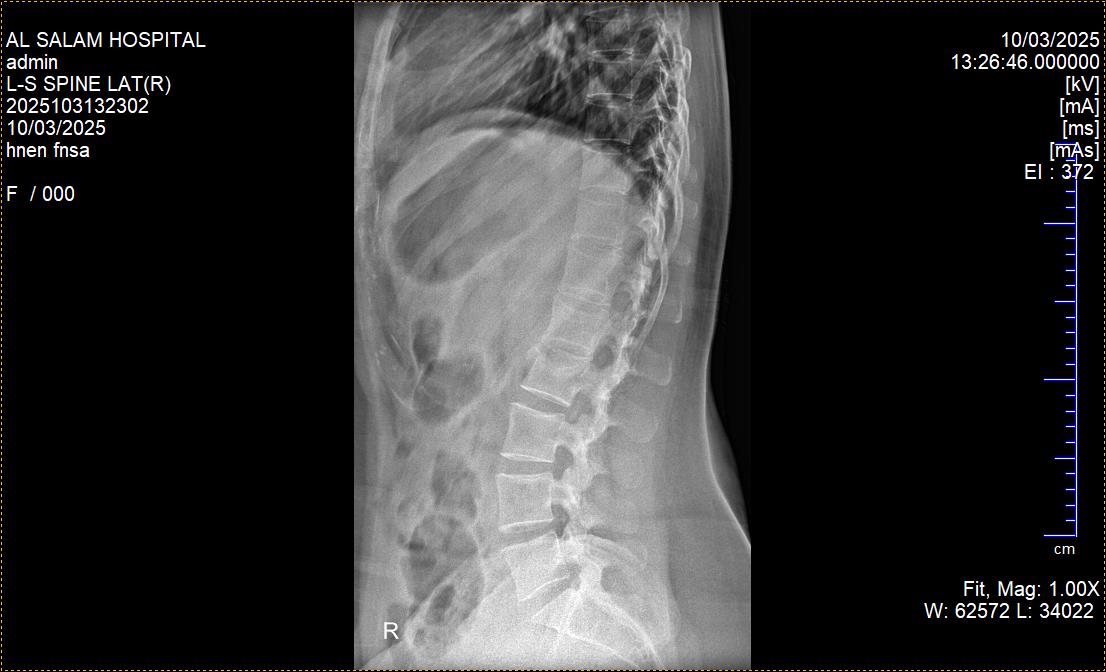

ما هو تقييم الأطباء ونتائج الصور الشعاعية الجديدة التي أجريتها بعد شهر من الالتزام بالراحة والاستلقاء واستخدام المشد الحديدي لعلاج كسر الفقرة القطنية الثانية (L2)، وهل تشير هذه النتائج إلى وجود تحسن في حالة الكسر والتعافي؟

جيد مافيش رجوع للجدار الخلفي ولا تضييق على قناة النخاع و اعراض التجبر بدات تظهر لكن يجب الالتزام بالراحة ومواصلة ارتداء الدعامة 0 2025-11-05T03:51:44+00:00

جيد مافيش رجوع للجدار الخلفي ولا تضييق على قناة النخاع و اعراض التجبر بدات تظهر لكن يجب الالتزام بالراحة ومواصلة ارتداء الدعامة